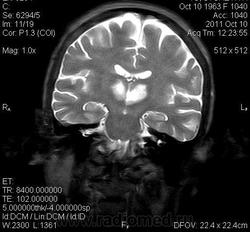

женщина 1963 года рождения. давность заболевания 10 дней.

ОНМК в бассейне правой и левой СМА (центральные ветви), подострый период.. Билатеральность нарушений может быть обусловлена вариантом строения Виллизиева круга.

Билатеральный таламический инфаркт. Либо венозный, либо вследствие закупорки одной из ветвей задней мозговой артерии - ЗМА (вариан развития ЗМА). Но не средней мозговой артерии (СМА). Мне представляеться, что здесь второе... За венозный инфаркт данных не вижу.

Я неприклонен... Инфаркт ЗМА (вероятно, варианта развития левой ЗМА - эмболии, мойа-мойа..).